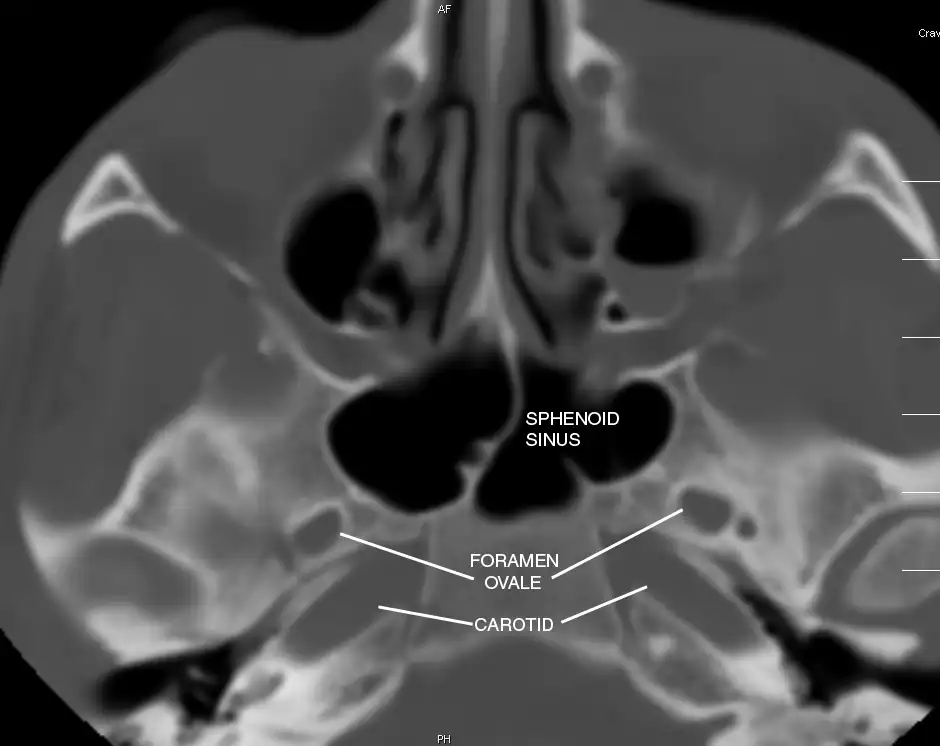

Sphenoid Sinus has 12 close structures: II, III, IV, V1, V2, VI, Vidian Nerve, Carotid artery, Brain, Dura, Pituitary.

Pertinent Sinonasal Anatomy

- V2 = Maxillary division, Trigeminal Nerve: exits foramen rotundum, superomedial to V3's foramen ovale.

- C = Carotid Artery: often with bony dehiscence into sphenoid. Together with CN II forms opticocarotid recess.

Sinus communicates posteriorly, so thrombosis is bilateral.